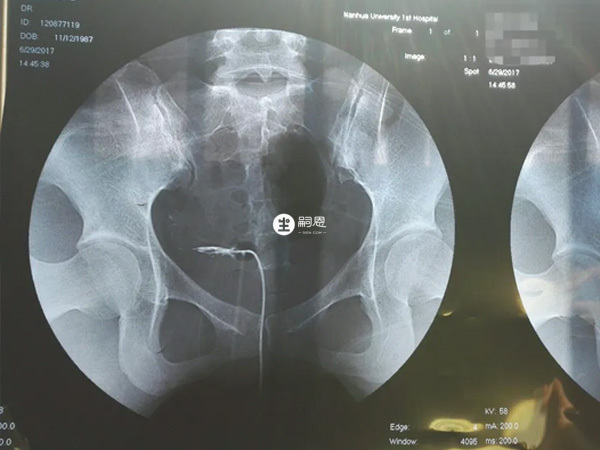

如果輸卵管存在狹窄、堵塞等情況,可能需要進行第三次輸暖管造影,以明確輸卵管是否存在疾病。所以輸卵管造影要推幾次,完全是結合實際情況而定的。運用輸卵管造影HSG通常會推1-3次藥水,推了3次藥水才顯影不一定就代表是堵塞了,需要結合顯影的情況來判定,但若是多次推入藥水之後不顯影則考慮為輸卵管近端堵。輸卵管造影檢查過程比較簡單,只要在將40%的碘油通常宮頸導管推入,然後在X線透視下觀察碘油流經輸卵管以及宮腔情況並拍片即可,期間多數患者是推2次造影劑,每次大約20~30ml。

輸卵管造影現在有傳統的HSG輸卵管造影以及超聲下HyCoSy輸卵管造影,HSG造影在推入1-3次造影劑後,需要結合造影劑在子宮腔、雙側輸卵管的彌散長度以及充盈時間,來綜合判斷雙側輸卵管是否通暢: